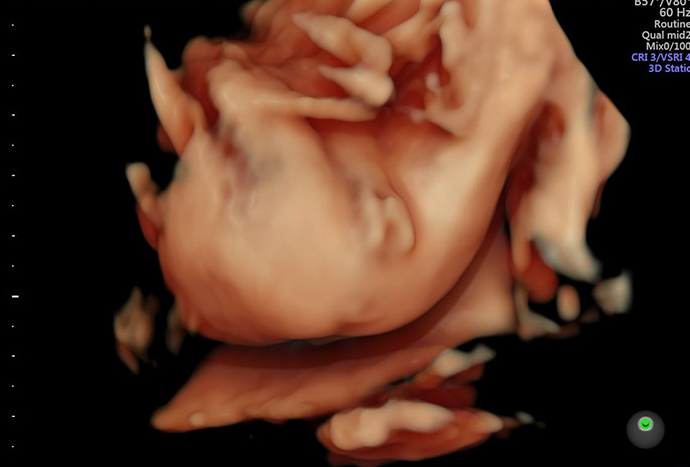

Do đó, khi bé khép chân sẽ cản trở việc xác định giới tính của thai nhi nên không thể dựa trên cách bé khép chân trong hình ảnh siêu âm mà kết luận đó là trai hay gái. Có thể xác định giới tính của thai nhi thông qua siêu âm trong giai đoạn thai kỳ nhất định, thông thường từ tuần thai thứ 18 đến 20 trở đi. Trong quá trình siêu âm, bác sĩ sẽ xác định giới tính là nam hay nữ bằng cách kiểm tra các đặc điểm về giới tính như cấu trúc sinh dục bên trong và ngoài của thai nhi.

Ngày nay, các phương pháp siêu âm hiện đại như siêu âm 4D, siêu âm 5D cho phép bác sĩ có thể dựa vào hình ảnh siêu âm ghi được để phán đoán giới tính của thai nhi dù em bé có khép chân khi siêu âm hay không.

Tình trạng bé khép chân khi siêu âm không cho bác sĩ nhìn thấy giới tính khá phổ biến. Thông thường, nguyên nhân là do tư thế nằm của bé trong tử cung của mẹ. Bé nằm nghiêng một bên với hai chân khép lại với nhau nên che mất bộ phận sinh dục dẫn đến những trường hợp siêu âm nhầm giới tính thai nhi.

Tuy các phương pháp siêu âm hiện đại như 4D, 5D đang được ứng dụng phổ biến nhưng tỷ lệ xác định chính xác giới tính thai nhi chỉ từ 80 - 95%. Ngoài nguyên nhânbé nằm chéo chân che đi bộ phận sinh dục, còn có những nguyên nhân khác gây khó khăn khi xác định giới tính thai nhi như dây rốn quấn che mất bộ phận sinh dục hay bộ phận sinh dục của bé phát triển chậm.